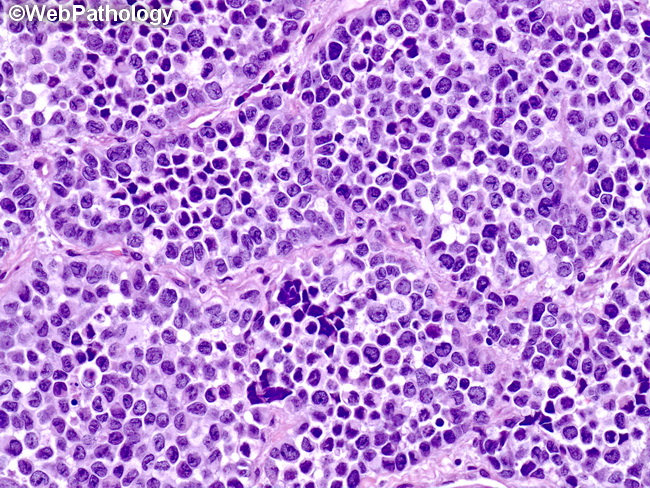

Soft Tissues: Alveolar Rhabdomyosarcoma

Webpathology.com: A Collection Of Surgical Pathology Images

rhabdomyosarcoma alveolar webpathology pathology

Webpathology.com: A Collection Of Surgical Pathology Images

rhabdomyosarcoma alveolar webpathology pathology comments microscopic

Webpathology.com: A Collection Of Surgical Pathology Images

rhabdomyosarcoma alveolar webpathology